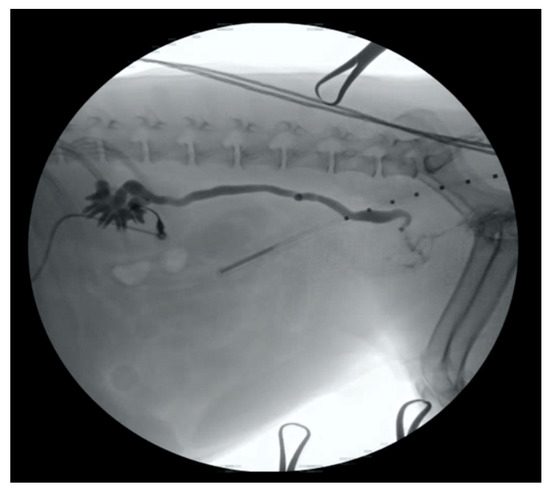

4.1. Ureter